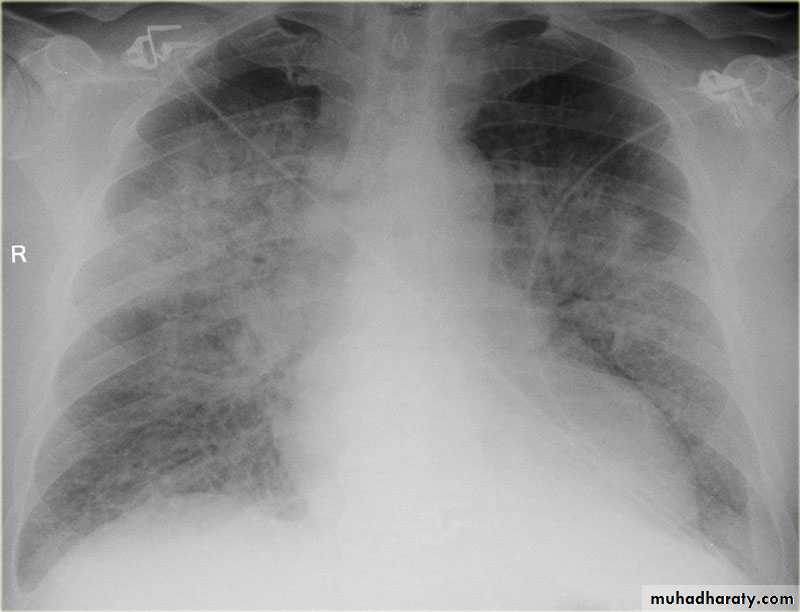

Pulmonary edema ( alveolar pulmonary edema)

Bat wing sign ( alveolar pulmonary edema)

39.pulmonary edema ( alveolar pulmonary edema )

40.batwing sign ( alveolar pulmonary edema )